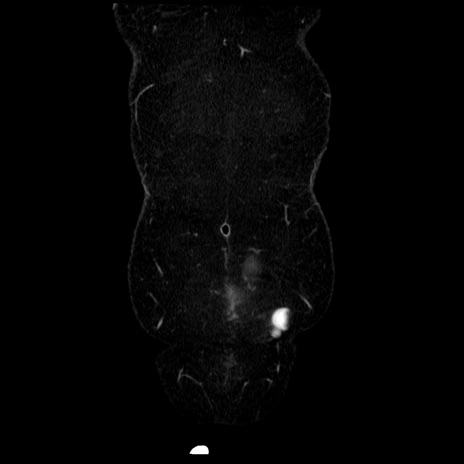

症例6(冠状断像)

【症例】50歳代女性

【主訴】下腹部痛

【現病歴】本日朝より下痢2回あり。 昼食を食べた後、嘔吐3回、下腹部痛認め、症状軽快せず、当院救急搬送。

最終食事:本日昼(生ものなし)。 昨日の夜、刺身を食ぺたとのこと。周囲に同様の症状の者なし。普段、排便は毎日あるとのこと。

【既往歴】卵巣癌術後(8年前に当院で卵巣摘出)

【身体所見】 意識清明、腹部:平坦、腸蠕動音→、やや硬、下腹部自発痛・圧痛あり、反跳痛あり、筋性防御なし。

【データ】WBC 16000、CRP 0.01